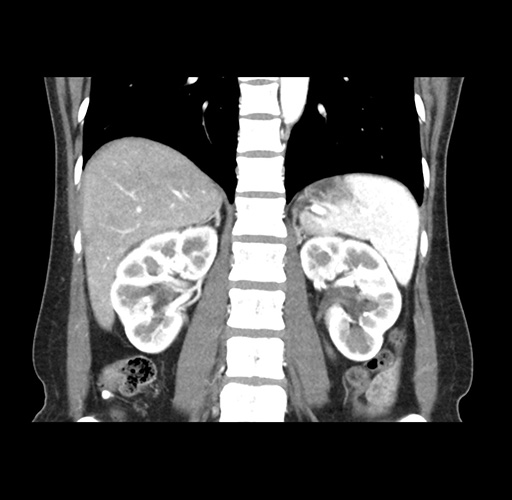

Imaging Analysis

Look through the patient's CT scan to identify any areas of concern for the necessary procedure.

Based on your CT findings, which issue(s) would give reason for "planned slowing down moment(s)" in this case?

Considering a standard left lateral sectionectomy procedure, what step(s) of the operation would you do differently in this case ?